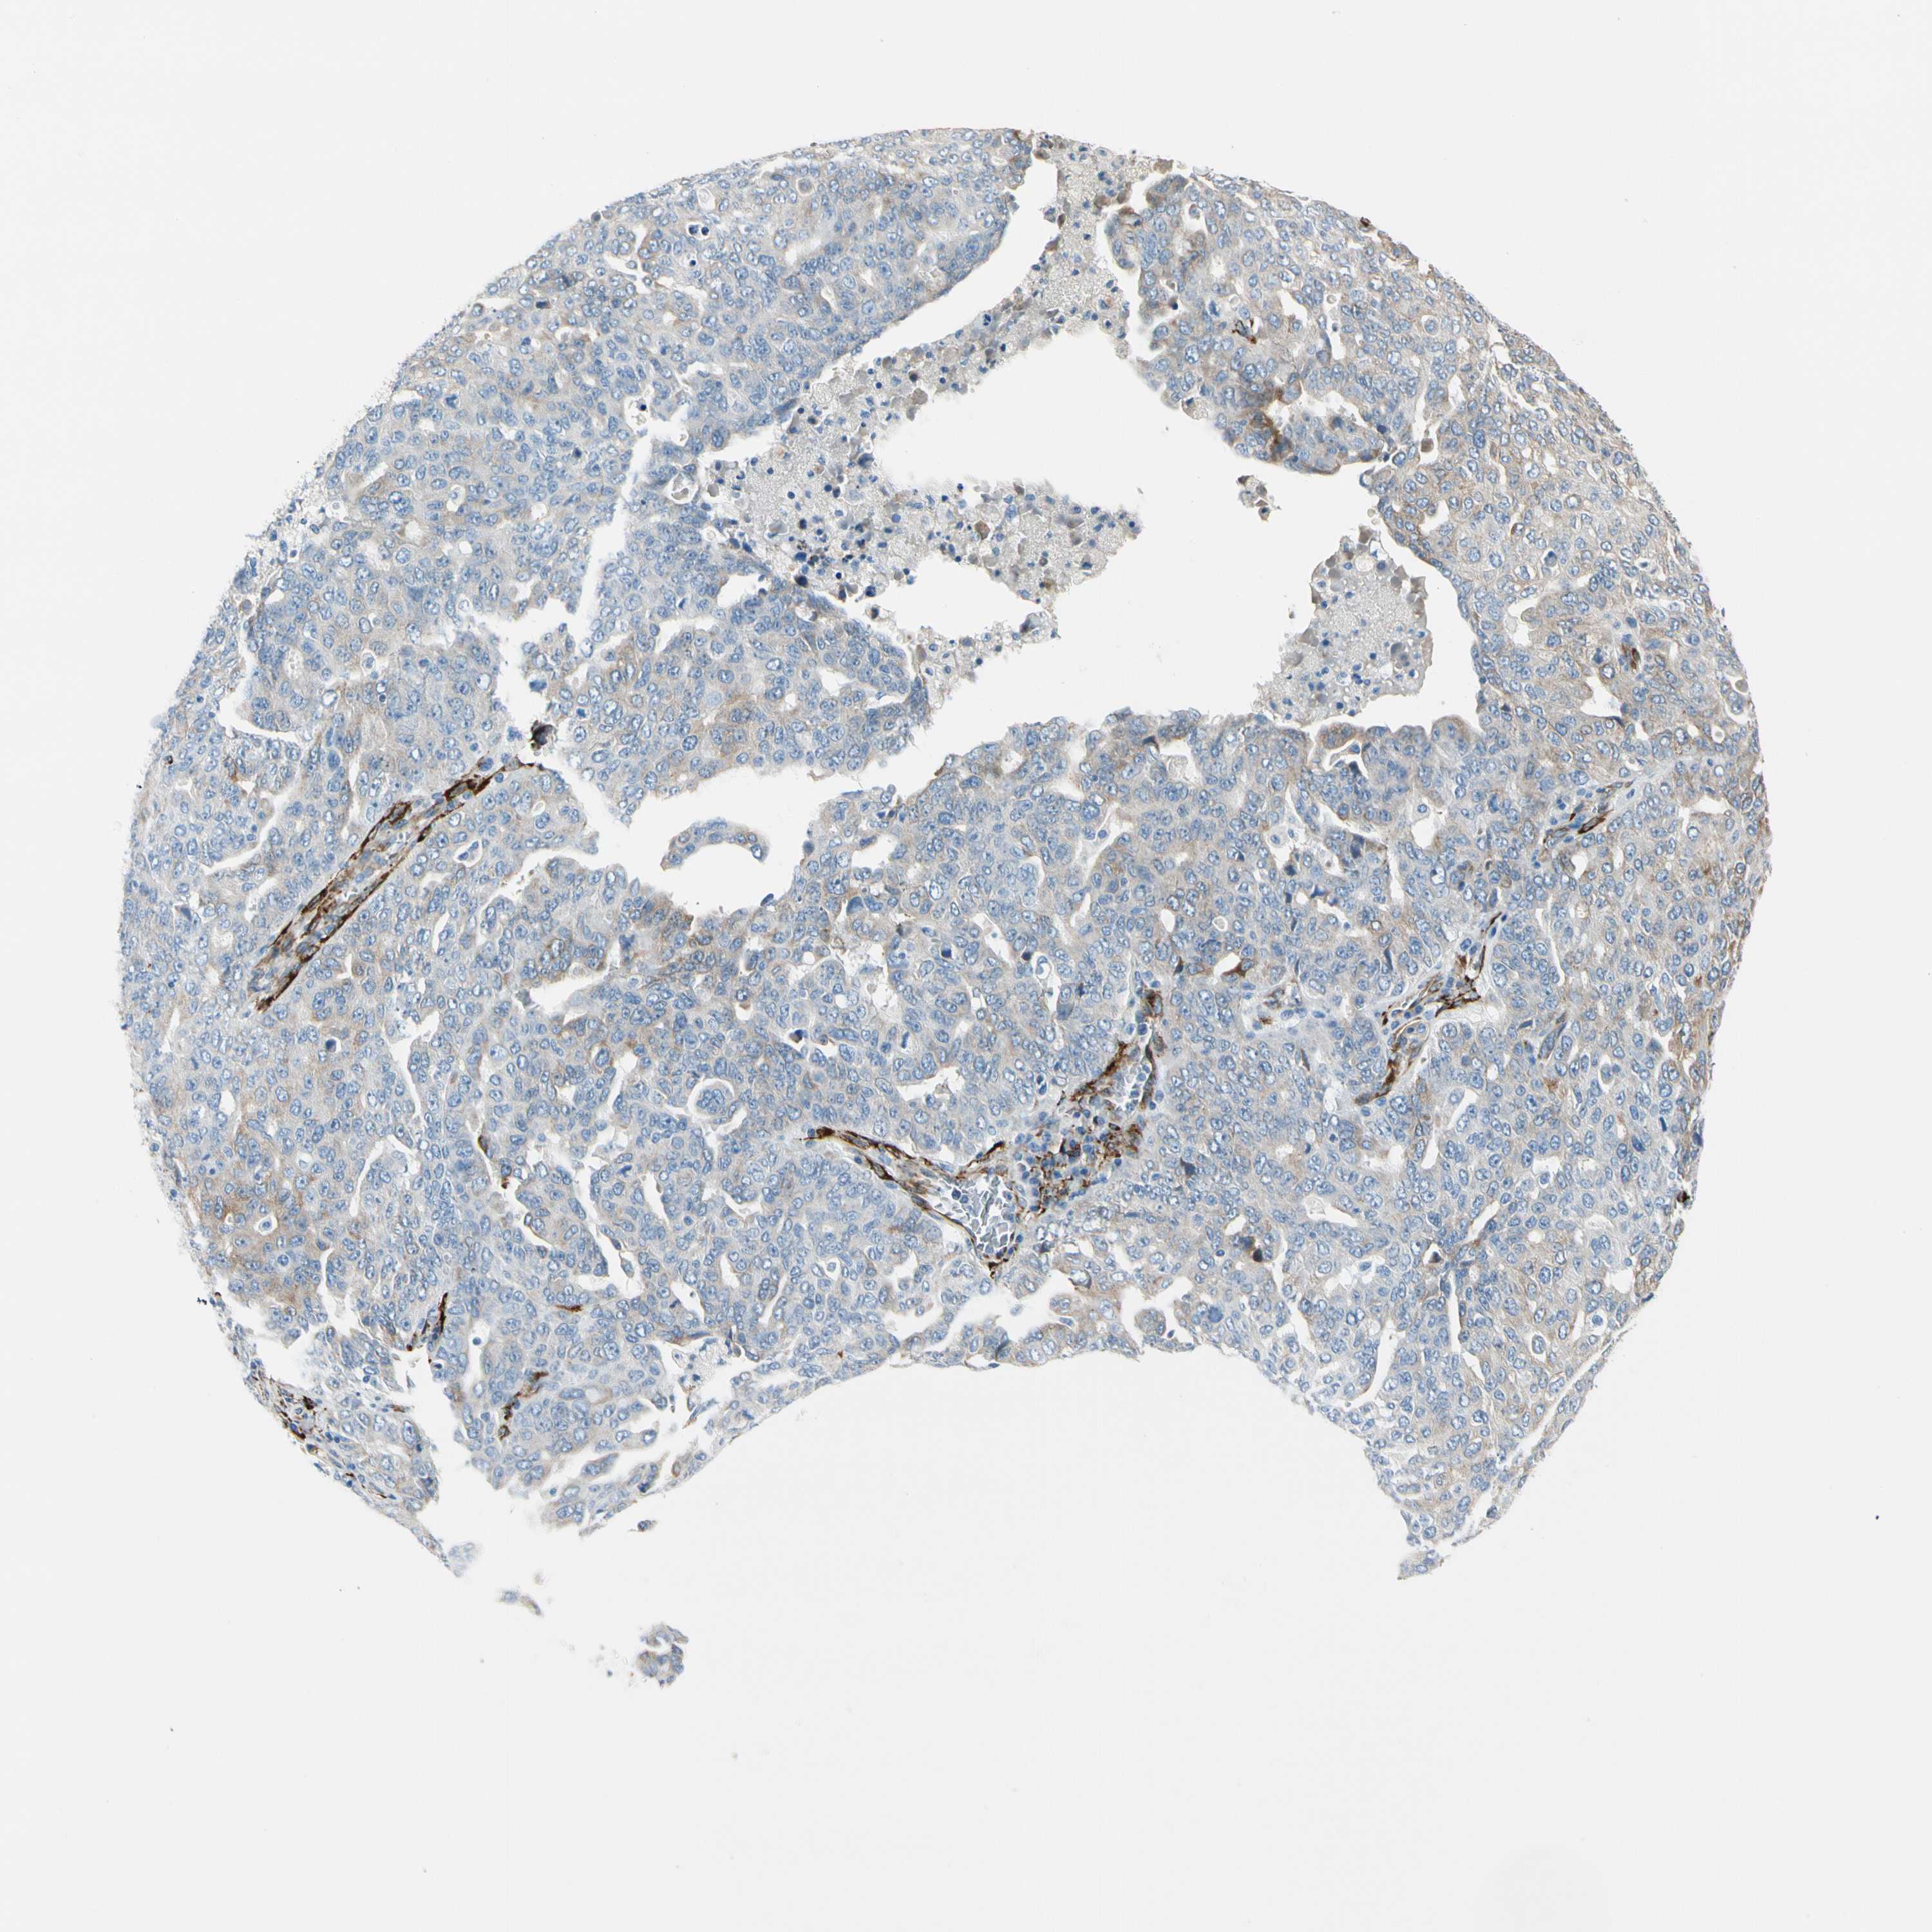

OVARIAN CANCER - Protein expressioni

A mouse-over function shows sample information and annotation data. Click on an image to view it in a full screen mode. Samples can be filtered based on level of antibody staining by selecting one or several of the following categories: high, medium, low and not detected. The assay and annotation is described here.

Note that samples used for immunohistochemistry by the Human Protein Atlas do not correspond to samples in the TCGA dataset.

Antibody stainingi

Antibody staining in the annotated cell types in the current human tissue is reported as not detected, low, medium, or high, based on conventional immunohistochemistry profiling in selected tissues. This score is based on the combination of the staining intensity and fraction of stained cells.

Each image is clickable and will lead to virtual microscopy that enables deeper exploration of all samples and also displays staining intensity scores, fraction scores and subcellular localization as well as patient and tissue information for each sample.

Antibody HPA008707

Staining

High

Medium

Low

Not detected

Intensity

Strong

Moderate

Weak

Negative

Quantity

>75%

75%-25%

<25%

None

Location

Nuclear

Cytoplasmic/membranous

Cytoplasmic/membranous,nuclear

Cystadenocarcinoma, serous, NOS

Carcinoma, endometroid

Cystadenocarcinoma, mucinous, NOS

Carcinoma, NOS